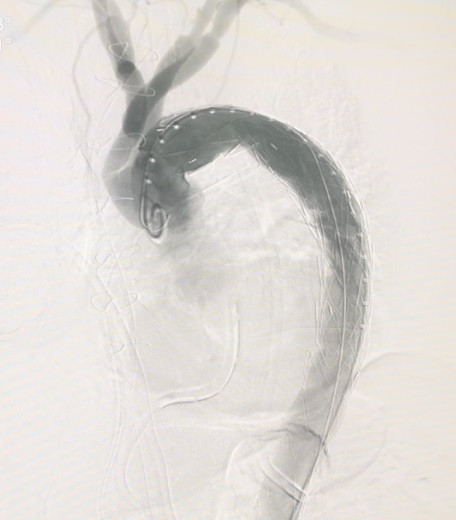

![]() |

| Phẫu thuật cho bệnh nhân lóc tách động mạch chủ tại Bệnh viện E. |